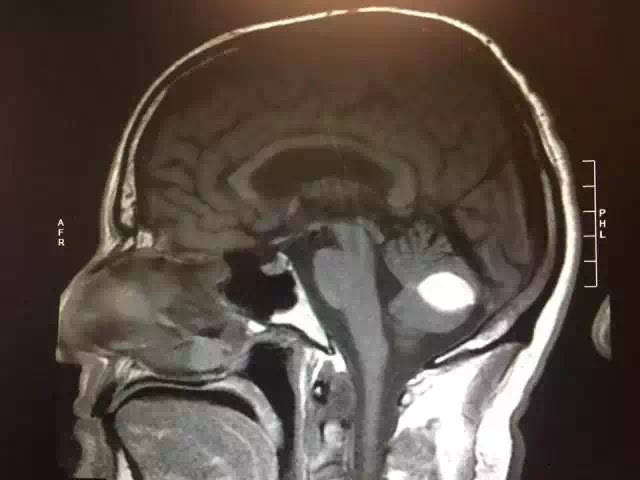

Ông Paul đã tìm đến rất nhiều bác sĩ. Một bác sĩ khoa giải phẫu thần kinh ở trường Đại học California, San Francisco cho rằng não của ông bị xuất huyết bên trong; còn một chuyên gia X-quang thì nói với ông rằng kết quả chụp cắt lớp vi tính cho thấy trong não của ông có khối u. Hai kết quả chẩn đoán này đều cần phải phẫu thuật.

➥ Khối u màu trắng trong não của ông Paul.

Không ngờ rằng một ngày trước ca phẫu thuật, khối u bên trong não của ông Paul đột nhiên “không cánh mà bay” và ca phẫu thuật nguy hiểm này bị hủy bỏ.

Các bác sĩ của Paul không thể giải thích được nguyên nhân của việc này, họ không biết chấm màu trắng hiện lên rõ ràng trong ảnh chụp cắt lớp vì sao lại biến mất. Được biết, họ còn yêu cầu ông Paul đến để nghiên cứu thêm nhằm biết được rốt cuộc đã xảy ra chuyện gì.